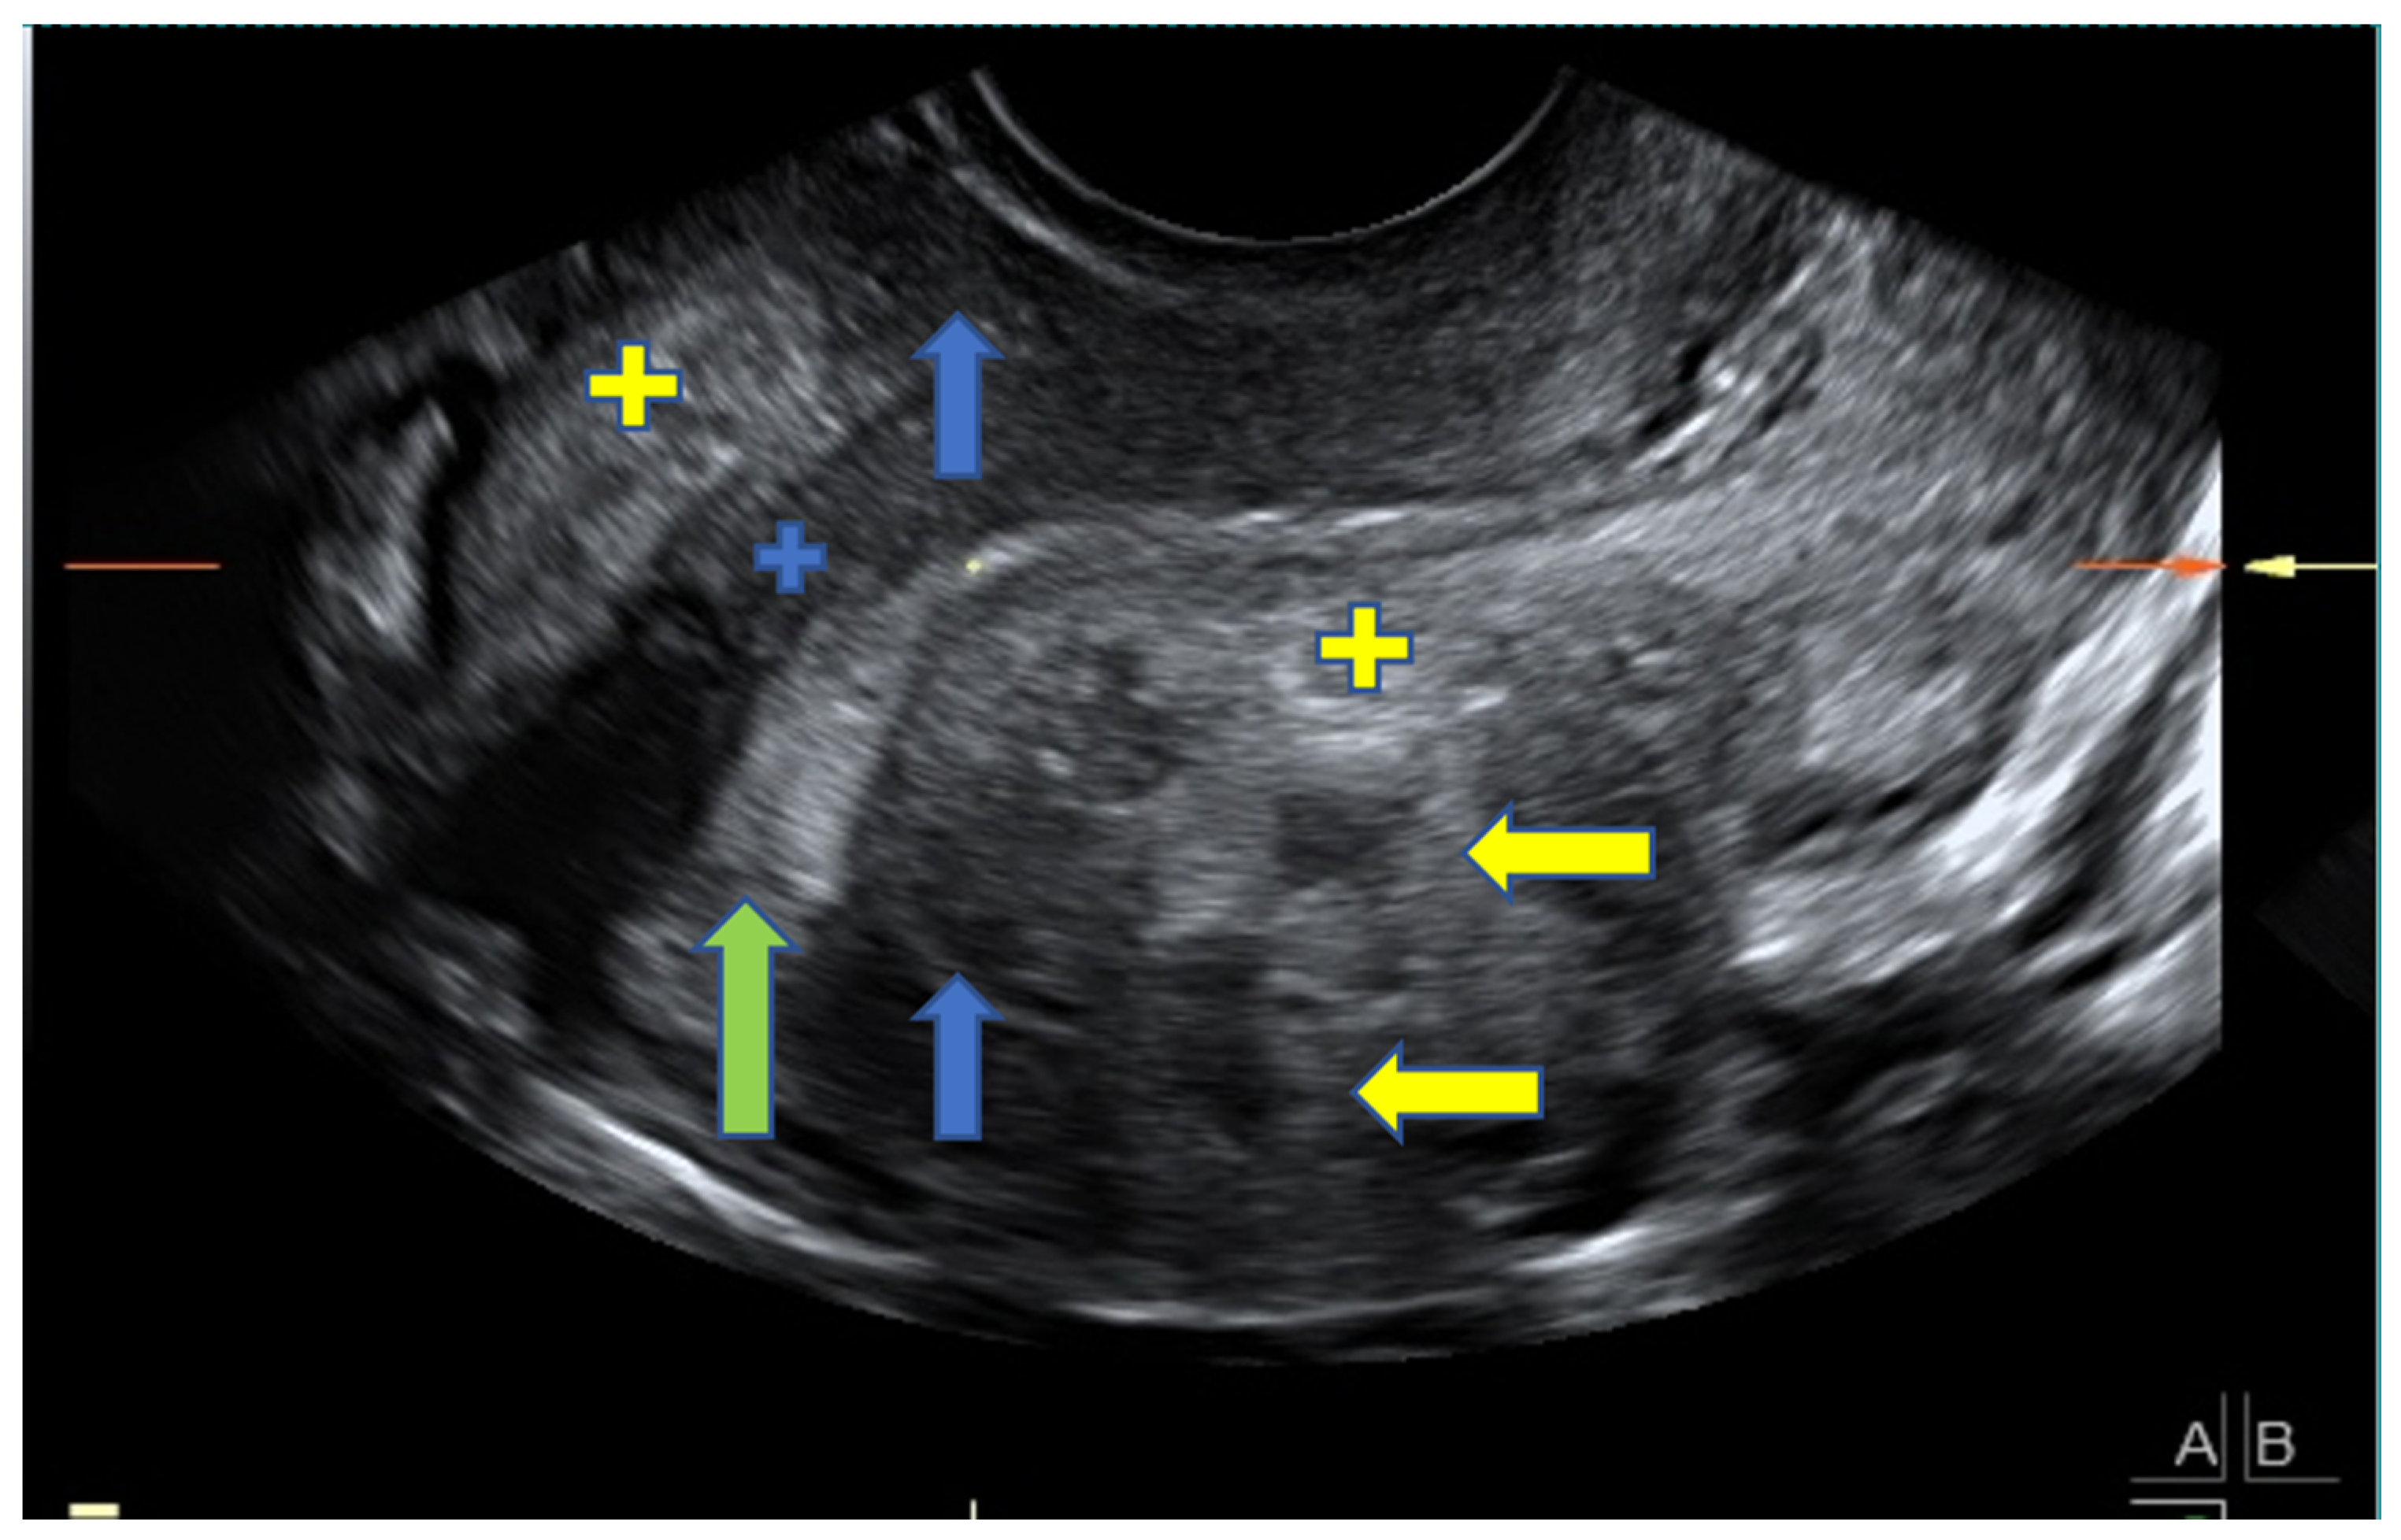

2.2. TVUS Evaluation of Adenomyosis and Endometriosis